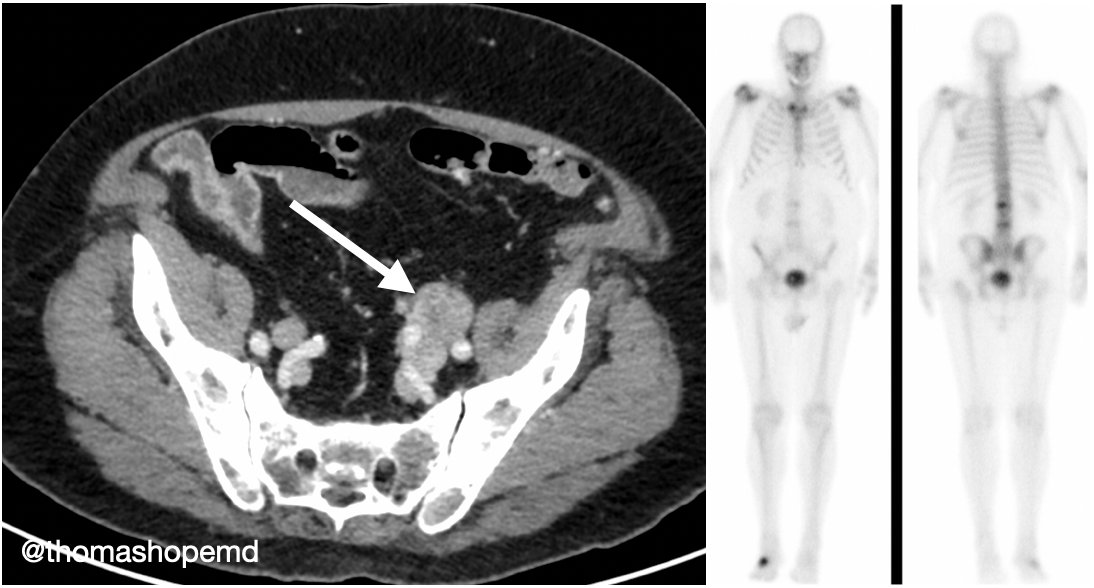

1/ Would you order a #PSMAPET in a patient post-RP with BCR and N1 disease on conventional imaging? What about this patient? PSA rose from 0.3 to over 50 in three years after surgery. 2.8 cm left pelvic node on CT with no other sites of disease including a negative bone scan.

3/ This patient received a #PSMAPET which showed an additional subcentimeter lesion in L4. The patient would have been treated with salvage RT, boost to the node, with ADT. What to do now is debatable, but if RT is performed, would likely include the bone lesion…